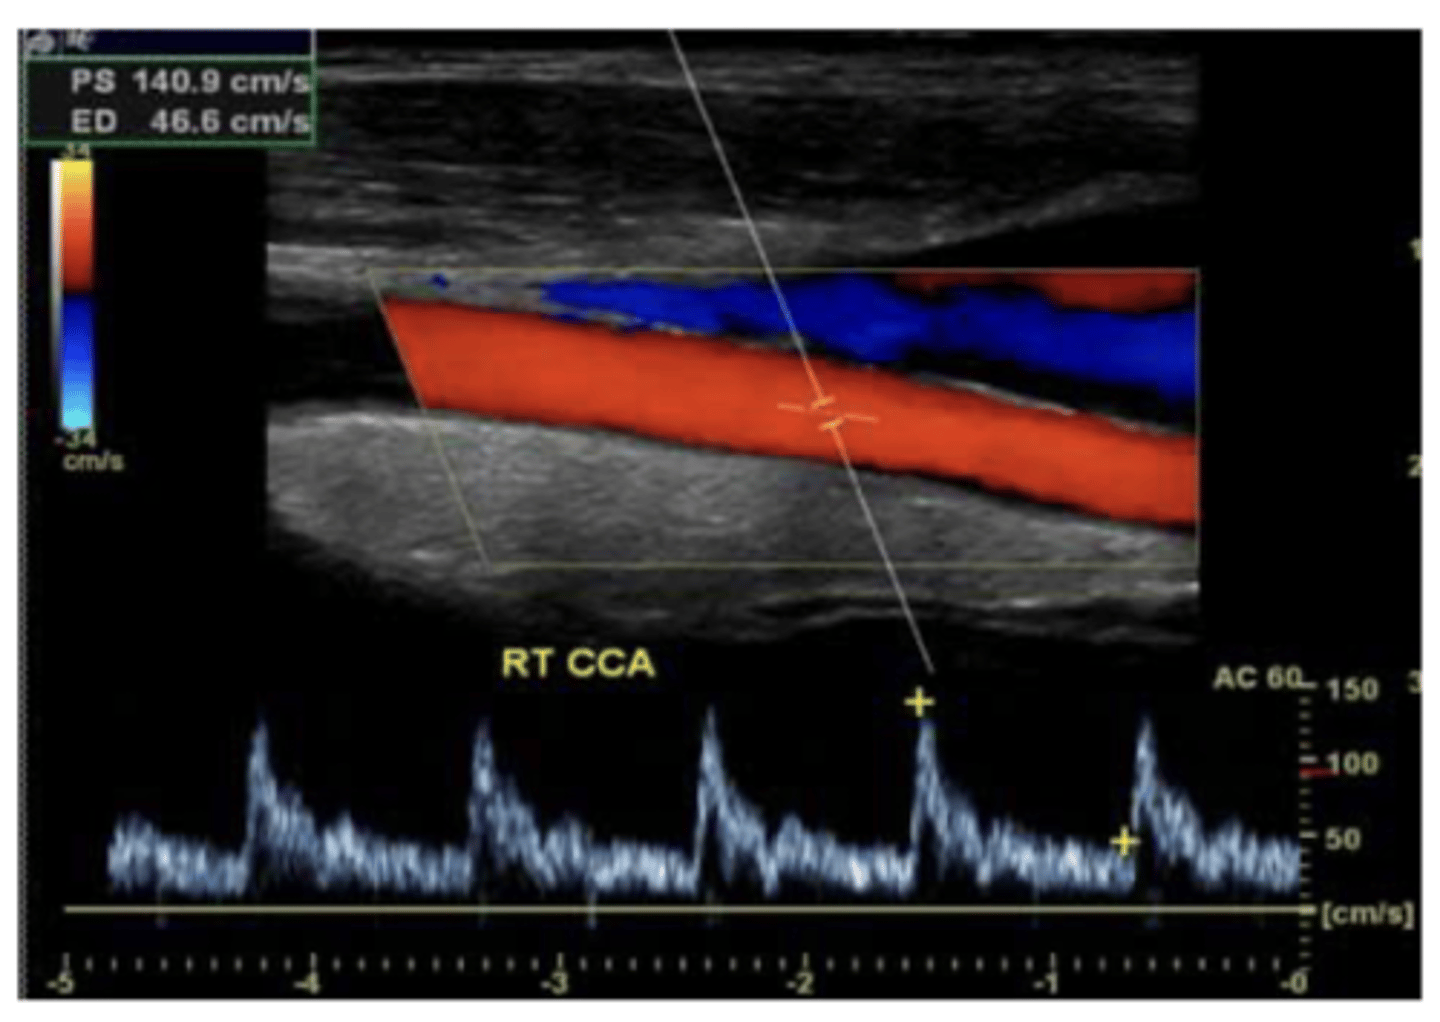

What is the gold standard for evaluating vessels? what is the down side of this testing, and what is used as first line study instead?

contrast angiography - invasive and carries risk of harm to pt

duplex u/s is first line study for vascular dz. can eval anatomy plus direction and magnitude of flow

<p>contrast angiography - invasive and carries risk of harm to pt</p><p>duplex u/s is first line study for vascular dz. can eval anatomy plus direction and magnitude of flow</p>